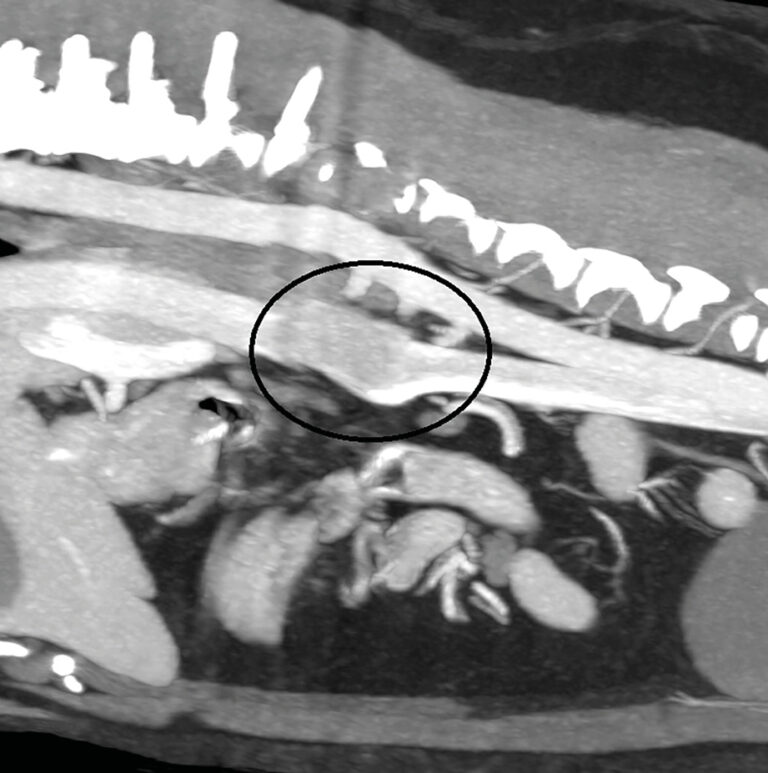

Los vermes pulmonares, que han sido subestimados durante mucho tiempo tanto en términos de prevalencia como de importancia para la salud de los gatos, son una posible causa de afección respiratoria. Estos parásitos pueden ser difíciles de diagnosticar y con frecuencia se omiten de la lista de diagnósticos diferenciales.